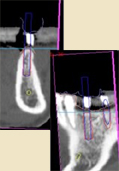

インプラント断面

意図的傾斜埋入をインプラント断面で診断可能

意図的傾斜埋入をインプラント断面で診断可能

インプラント体を中心とした断面が回転することで、隣在歯との相関やインプラント周囲の骨量と骨質を精度高く診断できるため、より安全な治療計画が立案可能になります。